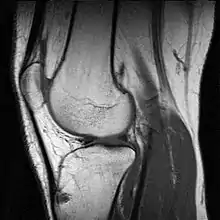

Imagerie

Il existe différentes modalités d'imagerie pour explorer la pathologie du genou. La radiographie, souvent réalisée en première intention permet d'examiner l'état des cartilages, les détachements osseux et d'éventuels bâillements en position de schuss (flexion légère). La goniométrie consiste en la réalisation d'une radiographie de l'ensemble de la jambe pour observer les déviations du genou.

L'arthrographie est réalisée à l'aide d'un produit de contraste injecté à l'intérieur de la capsule articulaire pour observer les ménisques et les ligaments. On l'associe souvent au scanner.

La tomodensitométrie ou scanner est une technique d'imagerie en coupe aux rayons X, qui permet de reconstituer le genou en 3D et ainsi visualiser les ligaments et les ménisques. Il est également possible de réaliser un arthroscanner qui consiste à injecter un produit de contraste comme dans l'arthrographie pour améliorer l'interprétation des images.

L'utilisation de l'échographie, à base d'ultrasons, est le meilleur moyen pour observer les tendons mais ne permet pas de constater les usures osseuses.

L'imagerie par résonance magnétique (IRM) permet d'observer tous les éléments de l'articulation. Elle est souvent réalisée en cas de rupture des ligaments

Enfin, la scintigraphie osseuse est une technique d'imagerie nucléaire réalisée à l'aide d'un produit radioactif pour observer le plus souvent l'état d'avancement de l'arthrose ou de la dégradation osseuse, notamment au niveau de l'articulation du genou.